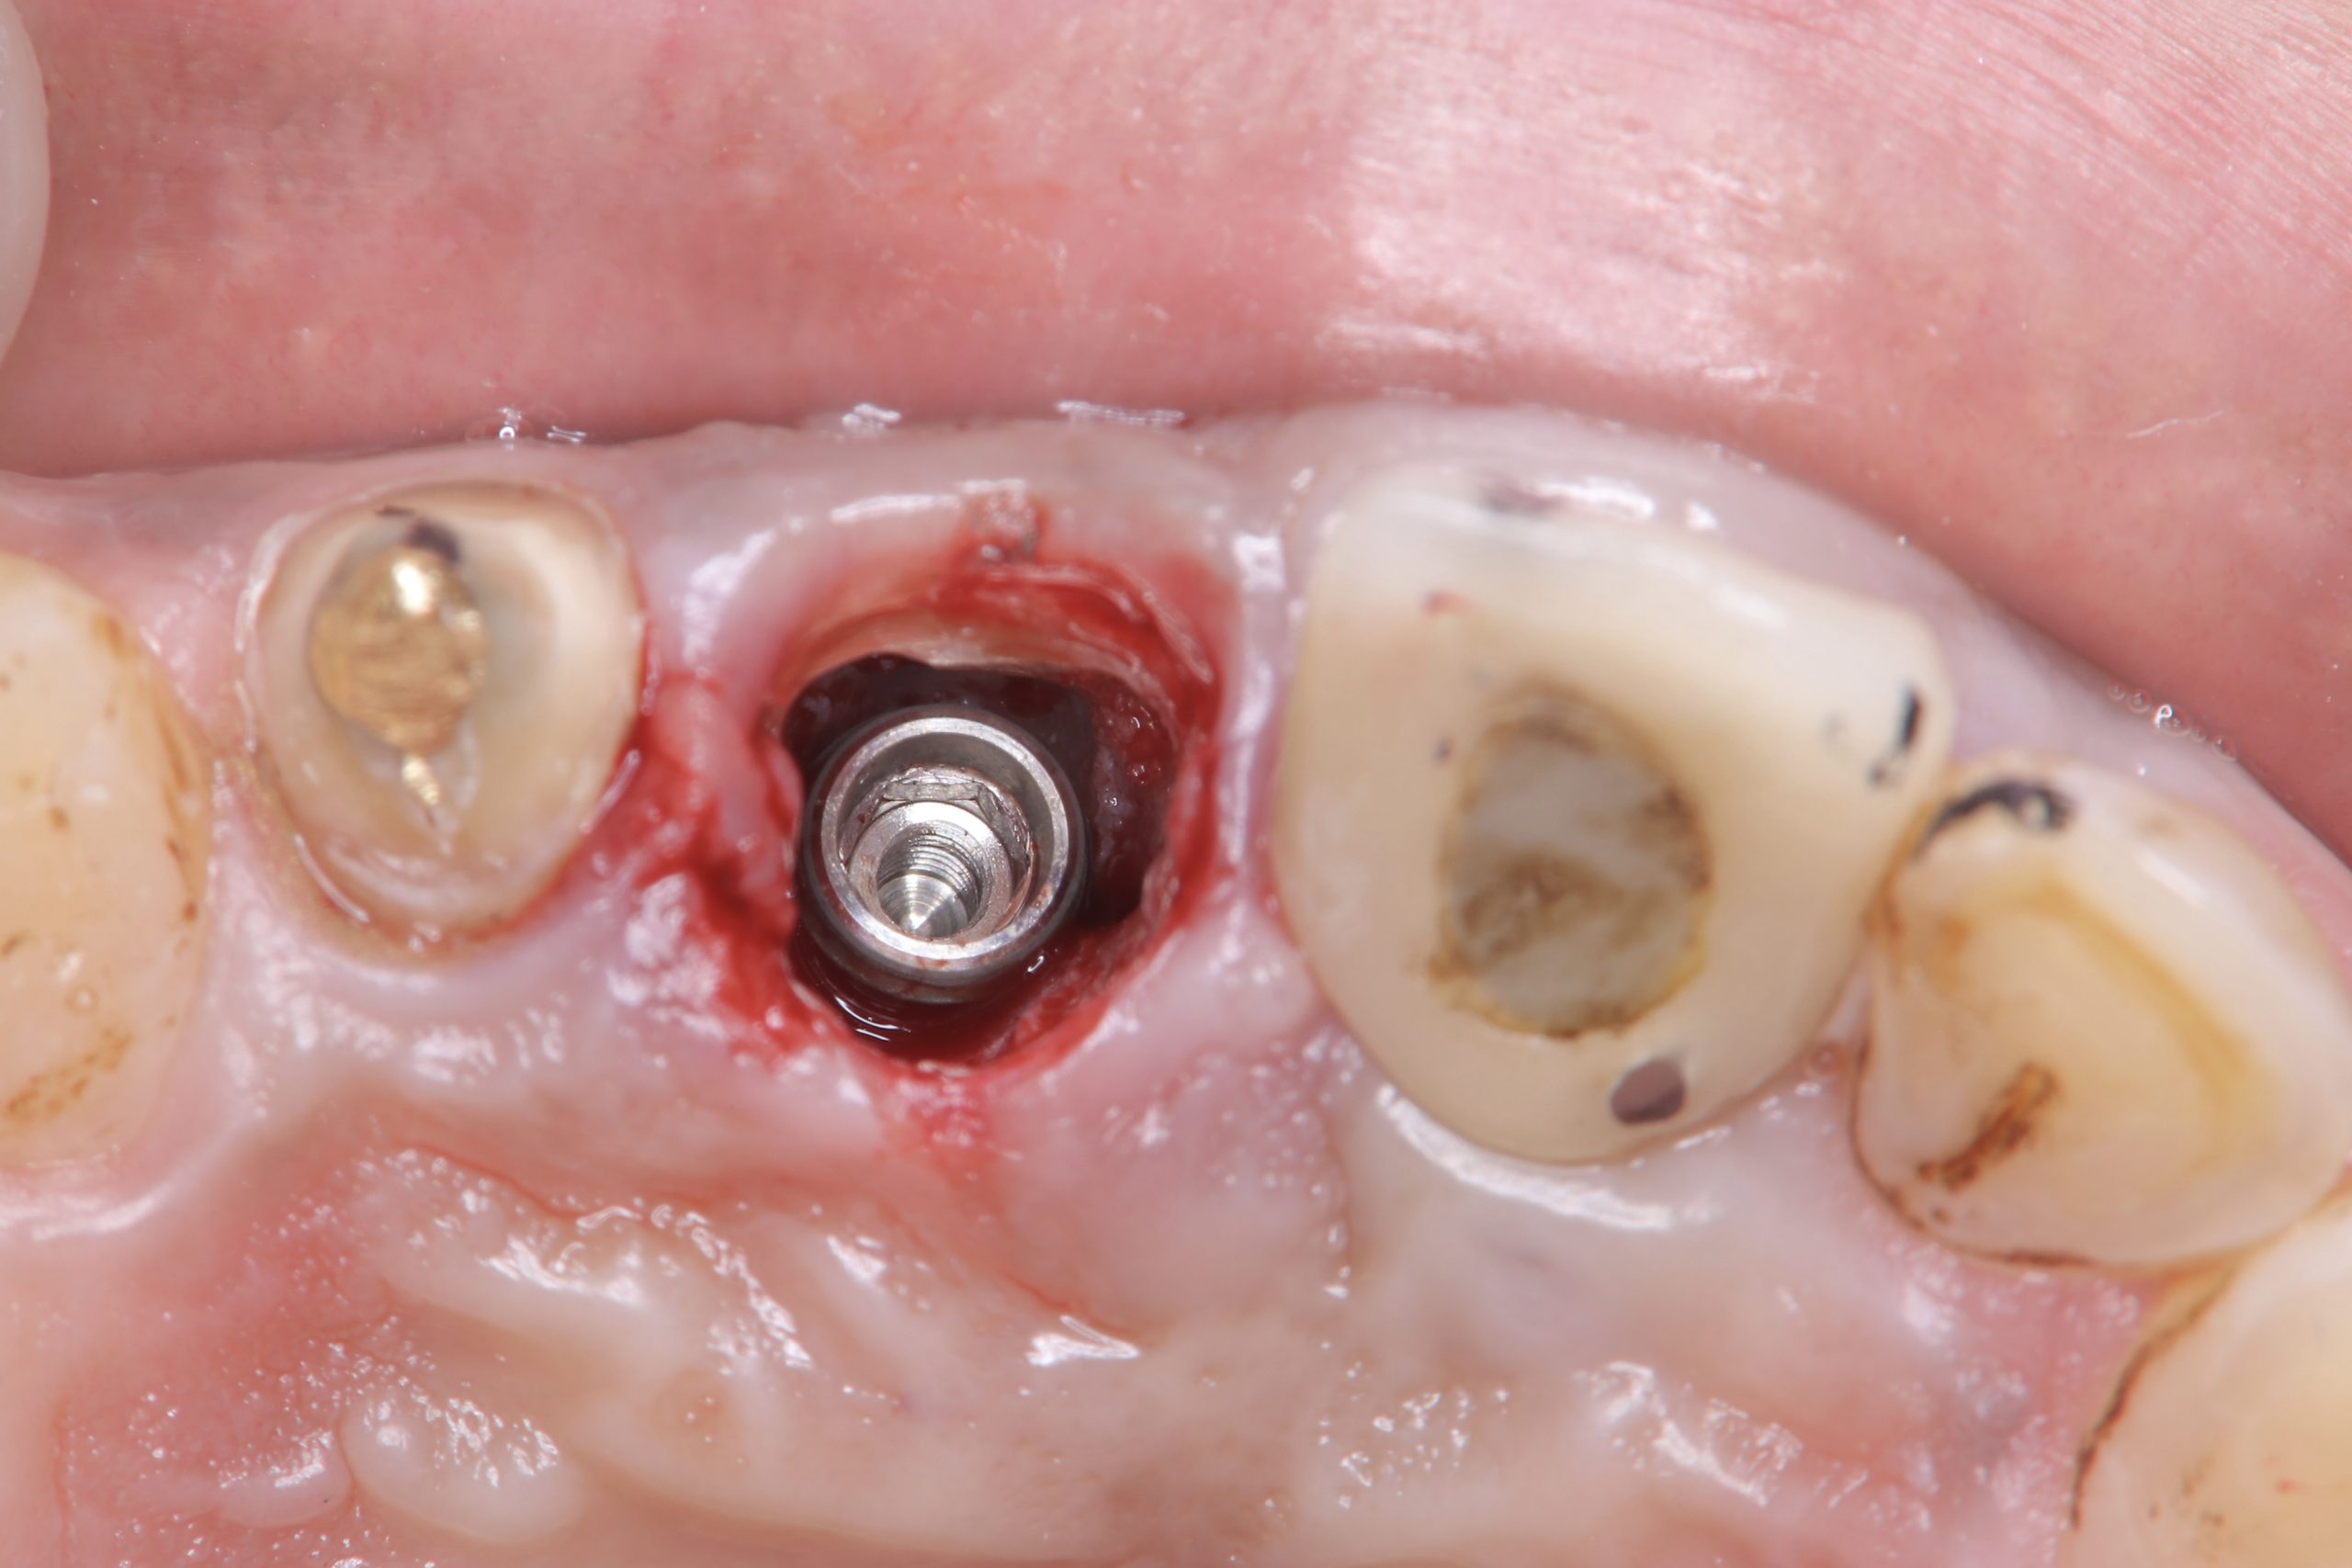

土曜日朝、前歯の抜歯即時

切歯管が近接しているから慎重にがテーマ!

その前に、部分抜歯し唇側束状骨の吸収を防ぐ!

色々な名称あり、ソケットシールドやらルートメンブレンやら他もあり